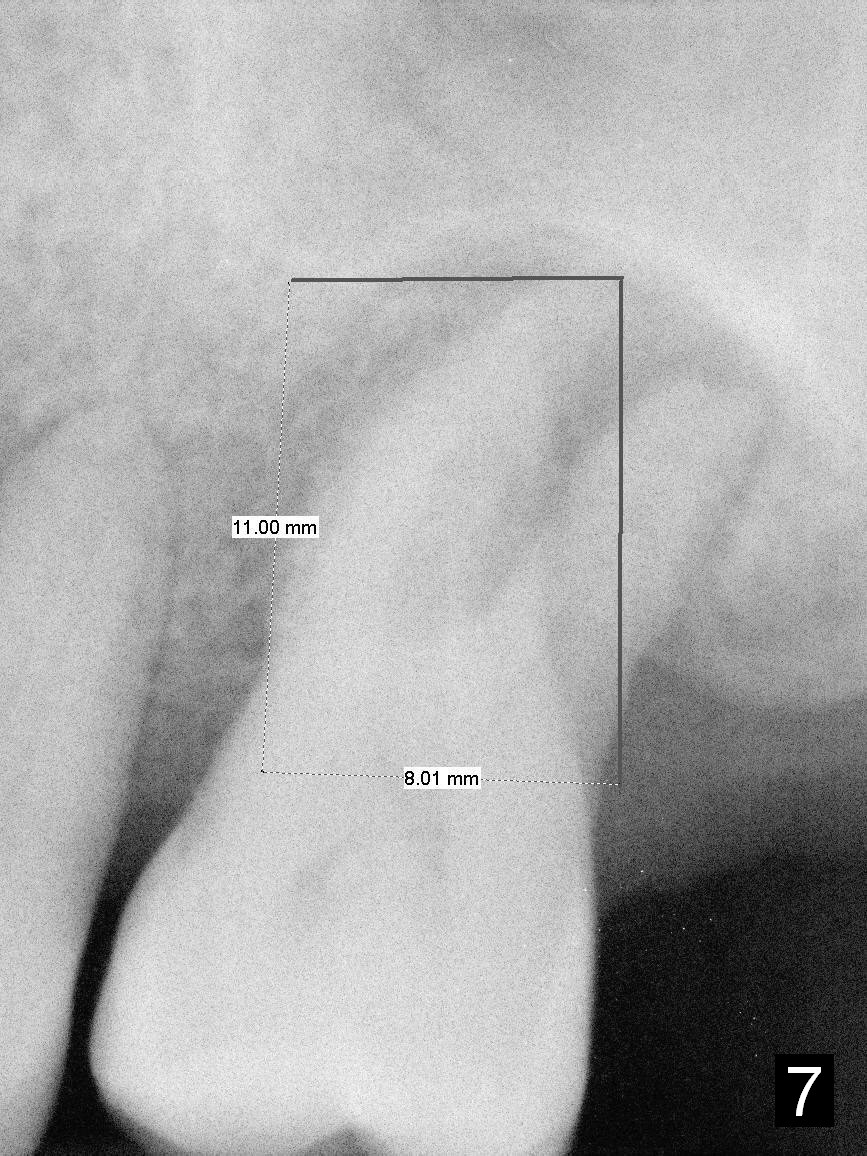

A large implant is place so that the mesiodistal dimension of the socket is obliterated by the implant (Fig.6 green circle). The buccal (Fib.5 B) and palatal gaps are filled with bone graft. It appears that either tapered (Fig4) or cylindrical (Fig.7) implant should be able to occupy the socket and obtain primary stability without perforating the sinus floor.